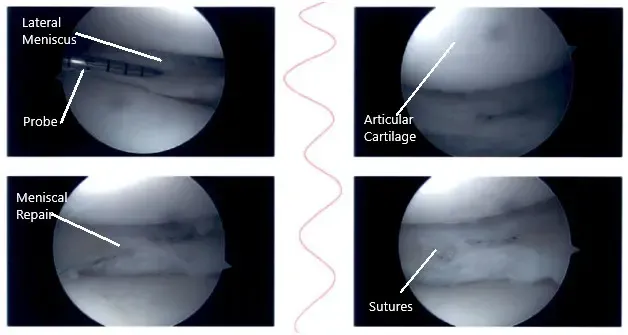

Intraoperative knee arthroscopic images.

The medial entry portal was made. The probe was inserted and the meniscus tear was again checked. It was involving the posterior body of the medial meniscus along with the capsule. The decision was made to repair the ramp lesion using an all-inside suture configuration.

Two curved and two reverse curved FasT-Fixes were used to complete the repair after the meniscus was abraded along with a capsule abrasion done with the shaver. The repair was found to be in a good position.